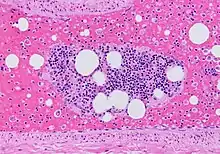

(A) After inhalation of 20 mCi of Xenon-133 gas, scintigraphic images were obtained in the posterior projection, showing uniform ventilation to lungs.

(B) After intravenous injection of 4 mCi of Technetium-99m-labeled albumin, scintigraphic images shown here in the posterior projection. This and other views showed decreased activity in multiple regions.

A ventilation/perfusion scan (or V/Q scan or lung scintigraphy) shows that some areas of the lung are being ventilated but not perfused with blood (due to obstruction by a clot).[18] This type of examination is as accurate as multislice CT, but is less used, due to the greater availability of CT technology. It is particularly useful in people who have an allergy to iodinated contrast, impaired kidney function, or are pregnant (due to its lower radiation exposure as compared to CT).[63][64][65] The test can be performed with planar two-dimensional imaging, or single photon emission computed tomography (SPECT) which enables three-dimensional imaging.[56] Hybrid devices combining SPECT and CT (SPECT/CT) further enable anatomic characterization of any abnormality.[66]